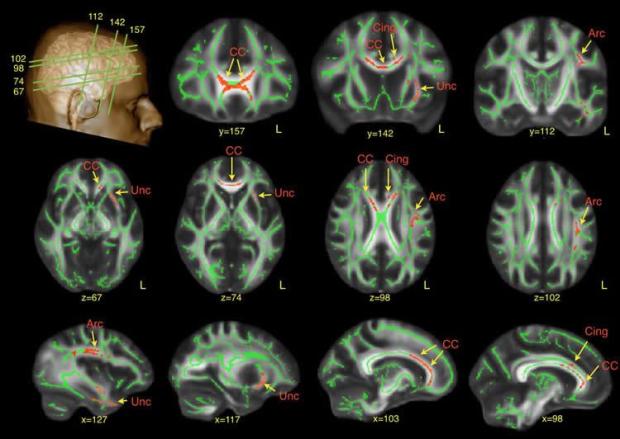

Red regions indicate reduced fractional anisotropy values in autism spectrum disorder (ASD). Credit: The researchers/King’s College London.

Research at King’s College London has revealed subtle brain differences in adult males with autism spectrum disorder (ASD), which may go some way towards explaining why symptoms persist into adulthood in some people with the disorder.